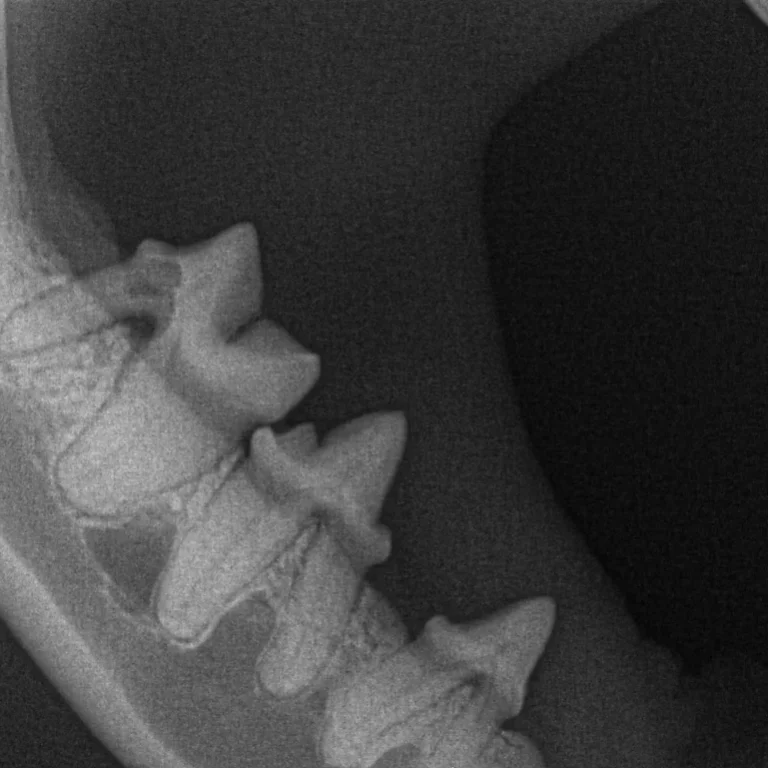

Dental radiographs are one of the most important diagnostic tools available to a veterinary dentist. They allow the internal anatomy of the teeth, the roots and the bone that surrounds the roots to be examined.